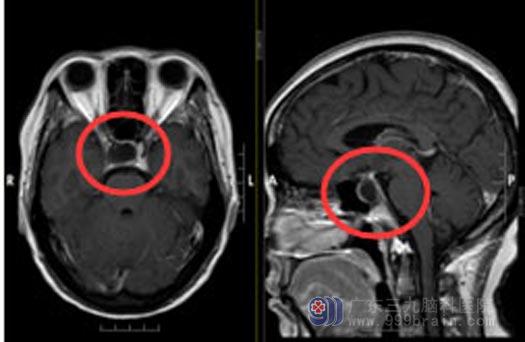

入院后,进一步脑部MR检查显示:鞍区占位性病变,考虑垂体瘤囊变,范围约2.3cm×1.9cm×2.2cm 。“医生,需要开颅吗,我非常害怕”,这是梁阿姨一直关心的问题。

▲手术前